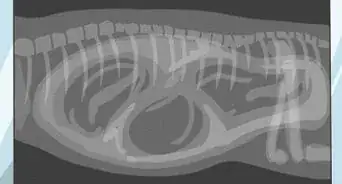

• The vet might use an endoscope, which is a fine tube with a fiberoptic camera, passing it up the nose to check that it is a foxtail that is causing the problem.

• The vet can remove the foxtail using forceps or a grasper on the endoscope. A vet's forceps will have much longer and narrower arms than tweezers at home.

• The vet might flush the nasal cavity to remove all nasal debris.

• Foxtail seeds can migrate and lodge in the spine, in the lungs, and in other internal organs. They enter through the nose, ears, paws, eyes, urethra or just through the skin and travel through the body. The seeds are very small, making locating them a painful, difficult, and expensive procedure. Depending on where a foxtail seed has traveled inside a dog, it can even be life threatening and will require prompt surgical removal.